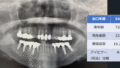

「お口年齢AI」は、歯科パノラマエックス線画像から、現在歯数、インプラント数、アイヒナーの咬合分類、歯槽骨吸収量などの抽出したデータと、生年月日・性別の情報から、「お口年齢」を算出するシステムとなっています。

この「お口年齢AI」システムは、エックス線画像の元データは必要なく、ディスプレイに映された画像をスマートフォンで撮影した写真で認識できるように開発しております。

本システムでは、生活習慣病である歯周病に関連する歯槽骨吸収量も加味して判定しており、また抜歯後にブリッジやインプラント治療を行った場合などは、顕著に「お口年齢」が若年指標として算出されます。